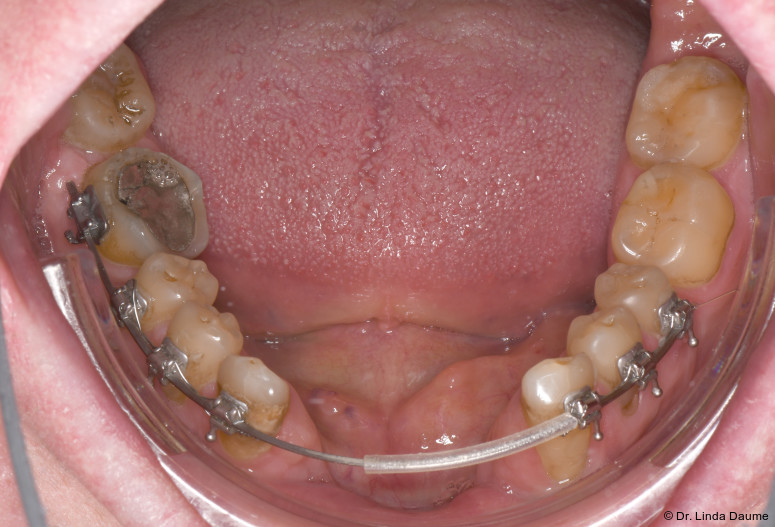

Nach einer Latenzphase von sieben Tagen begann die Distraktion mit 1 mm pro Tag, aufgeteilt in mehrere Einzelaktivierungen unter engmaschiger Kontrolle. Nach Erreichen der vorgesehenen Endposition begann die Konsolidierungsphase (Abb. 4). Der Distraktor wurde nach acht Monaten entfernt und es erfolgte die Implantation in Regio 32 und 42 mit lokaler Augmentation (Abb. 5a+b). Nach einer weiteren Einheilphase von fünf Monaten wurden die Implantate freigelegt und das Weichgewebe mittels eines freien Schleimhauttransplantats vom Gaumen optimiert. Die prothetische Versorgung konnte anschließend festsitzend mit einer implantatgetragenen Brücke von 32-42 realisiert werden (Abb. 6).